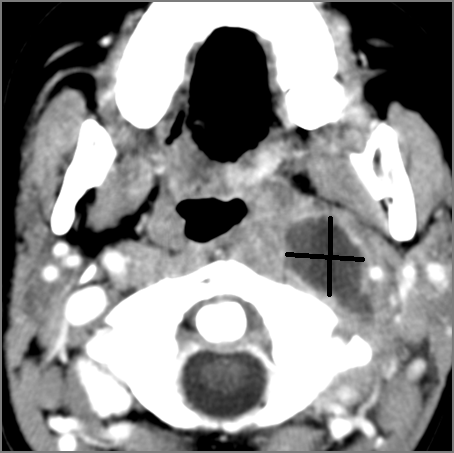

Hypopharynx, Larynx, Deep Neck and Entire Retropharyngeal Space

There is edema/abscess arising from the hypopharynx, larynx, thyroid gland or trachea.

There is edema/abscess within the adjacent deep neck, and/or retropharyngeal space.